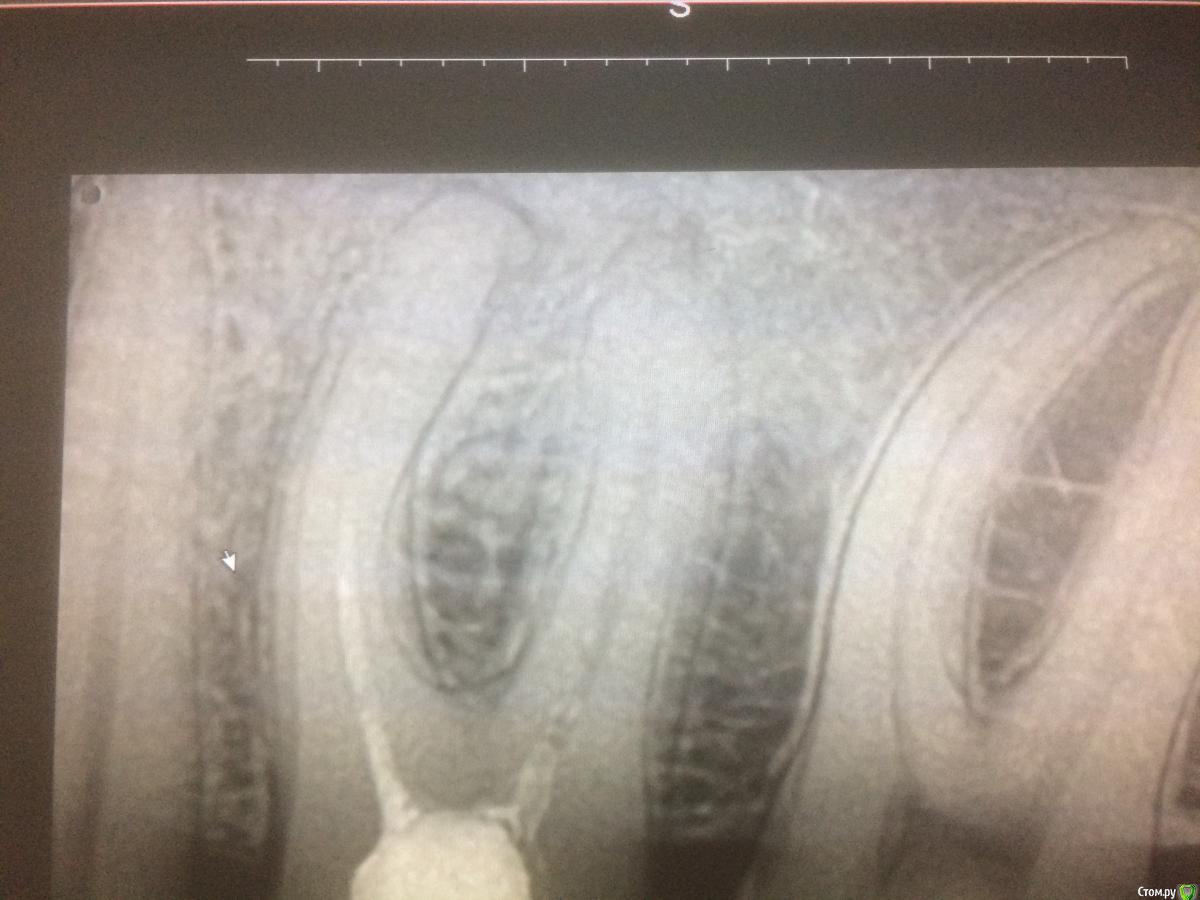

xMeDx Опубликовано 31 июля, 2019 Поделиться Опубликовано 31 июля, 2019 Начальная ситуация :пациент жалуется на застревание пиши между 4.5,4.6.Делаю снимок 4.6-большая пломба и слегка прикрыты устья дистального канала материалом а так канал пустой .Медиальные запломбированы на половину .Пломбировка рыхлая .На апексах легкое разряжение костной ткани.Легкая боль при перкуссии. Распломбировал,обработал химически.На неделю кальций и временная пломба.Через 5 дней пациент приходит с жалобами на ноющие боли которые особо и не беспокоят но спать не дают и обезболивающее 2 раза в день (это со слов пациента жалобы ).Открываю каналы.Обрабатываю .Закрываю постоянным тиэдент +гутта.Назначаю нпвс.Это вчера.Сегодня зуб болит так же.Причина просто реакция на кальций и нужно время или может быть что-то ещё ? Ссылка на комментарий

xMeDx Опубликовано 31 июля, 2019 Автор Поделиться Опубликовано 31 июля, 2019 покажите снимокСмущает ещё близость нижнечелюстного канала 1 Ссылка на комментарий

xMeDx Опубликовано 31 июля, 2019 Автор Поделиться Опубликовано 31 июля, 2019 (изменено) только это???????? Больше ничего не смущает?А что должно смущать?Материал в медиальных каналах недоведенный ? Изменено 31 июля, 2019 пользователем xMeDx Ссылка на комментарий

xMeDx Опубликовано 31 июля, 2019 Автор Поделиться Опубликовано 31 июля, 2019 (изменено) только это???????? Больше ничего не смущает?Или угол медиально язычного корня ? Изменено 31 июля, 2019 пользователем xMeDx Ссылка на комментарий